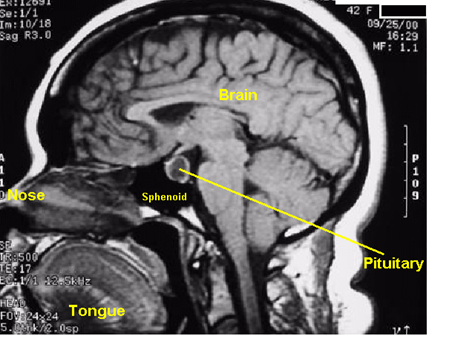

Common (10-20 % of brain tumors)

ages 30-40

(Anterior) Pituitary Adenomas

Gigantism in children and acromegaly in adults from increased ____

GH

Cushing’s disease increased _____ triggering the adrenal gland to increase production of steroid hormones

ACTH

Hyperthyroidism from too much ___

TSH